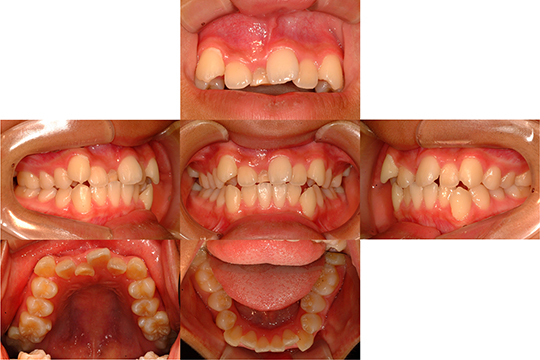

上顎左側中切歯逆性埋伏

逆性埋伏した上顎左側中切歯をリンガルアーチとセクシャナルアーチを

用いて開窓・牽引・排列した症例です

初診時〜治療中〜治療終了時(上段から下段へ)

上顎左側犬歯埋伏

上顎左側犬歯の埋伏に対して残存する上顎左側乳犬歯を抜歯して

上顎左側犬歯の萌出嚢胞を開窓後に牽引して排列を行った症例です

初診時

治療終了時

上顎左側犬歯を排列できました